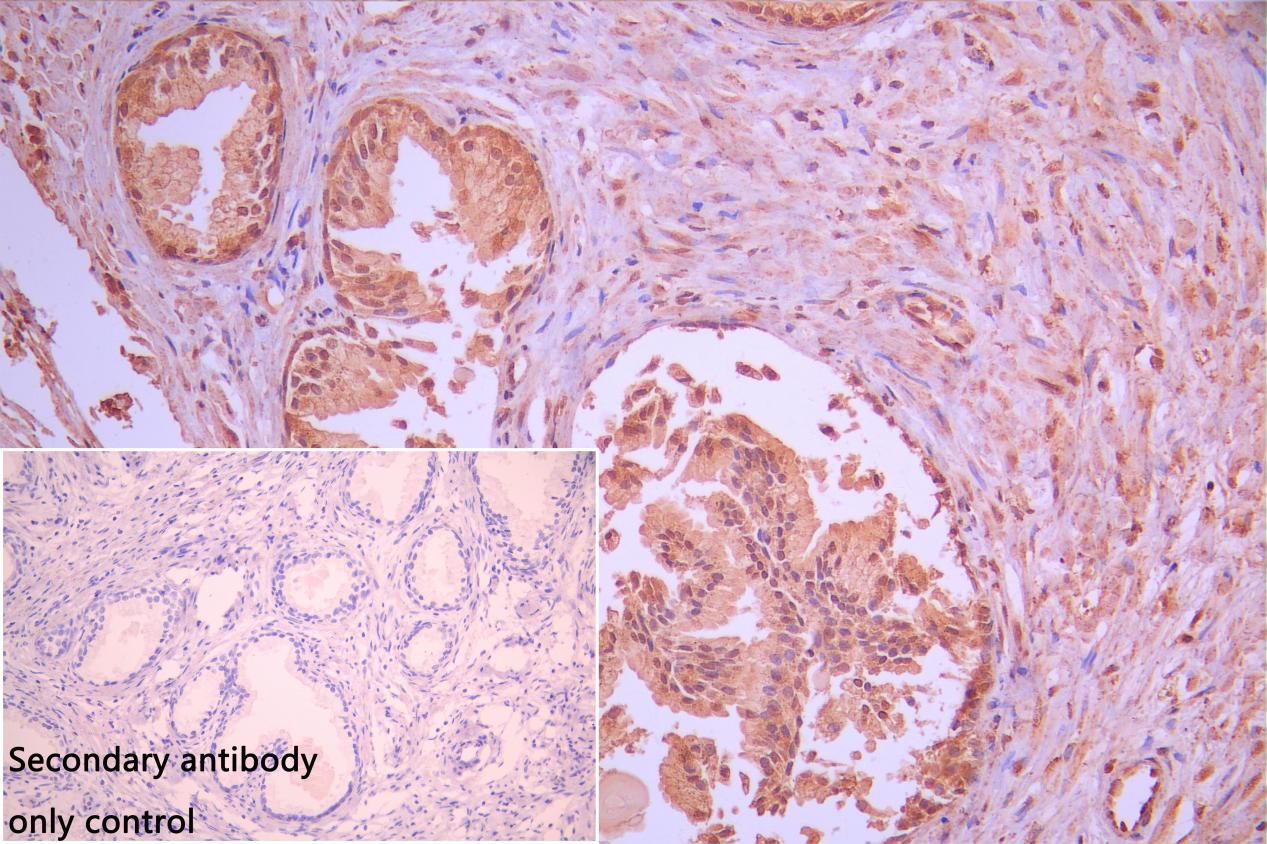

IHC image of CSB-PA622986LA01HU diluted at 1:50 and staining in paraffin-embedded human prostate tissue performed on a Leica BondTM system. After dewaxing and hydration, antigen retrieval was mediated by high pressure in a citrate buffer (pH 6.0). Section was blocked with 10% normal goat serum 30min at RT. Then primary antibody (1% BSA) was incubated at 4°C overnight. The primary is detected by a Goat anti-rabbit polymer IgG labeled by HRP and visualized using 0.05% DAB. Secondary antibody only control: uses 1% BSA instead of primary antibody